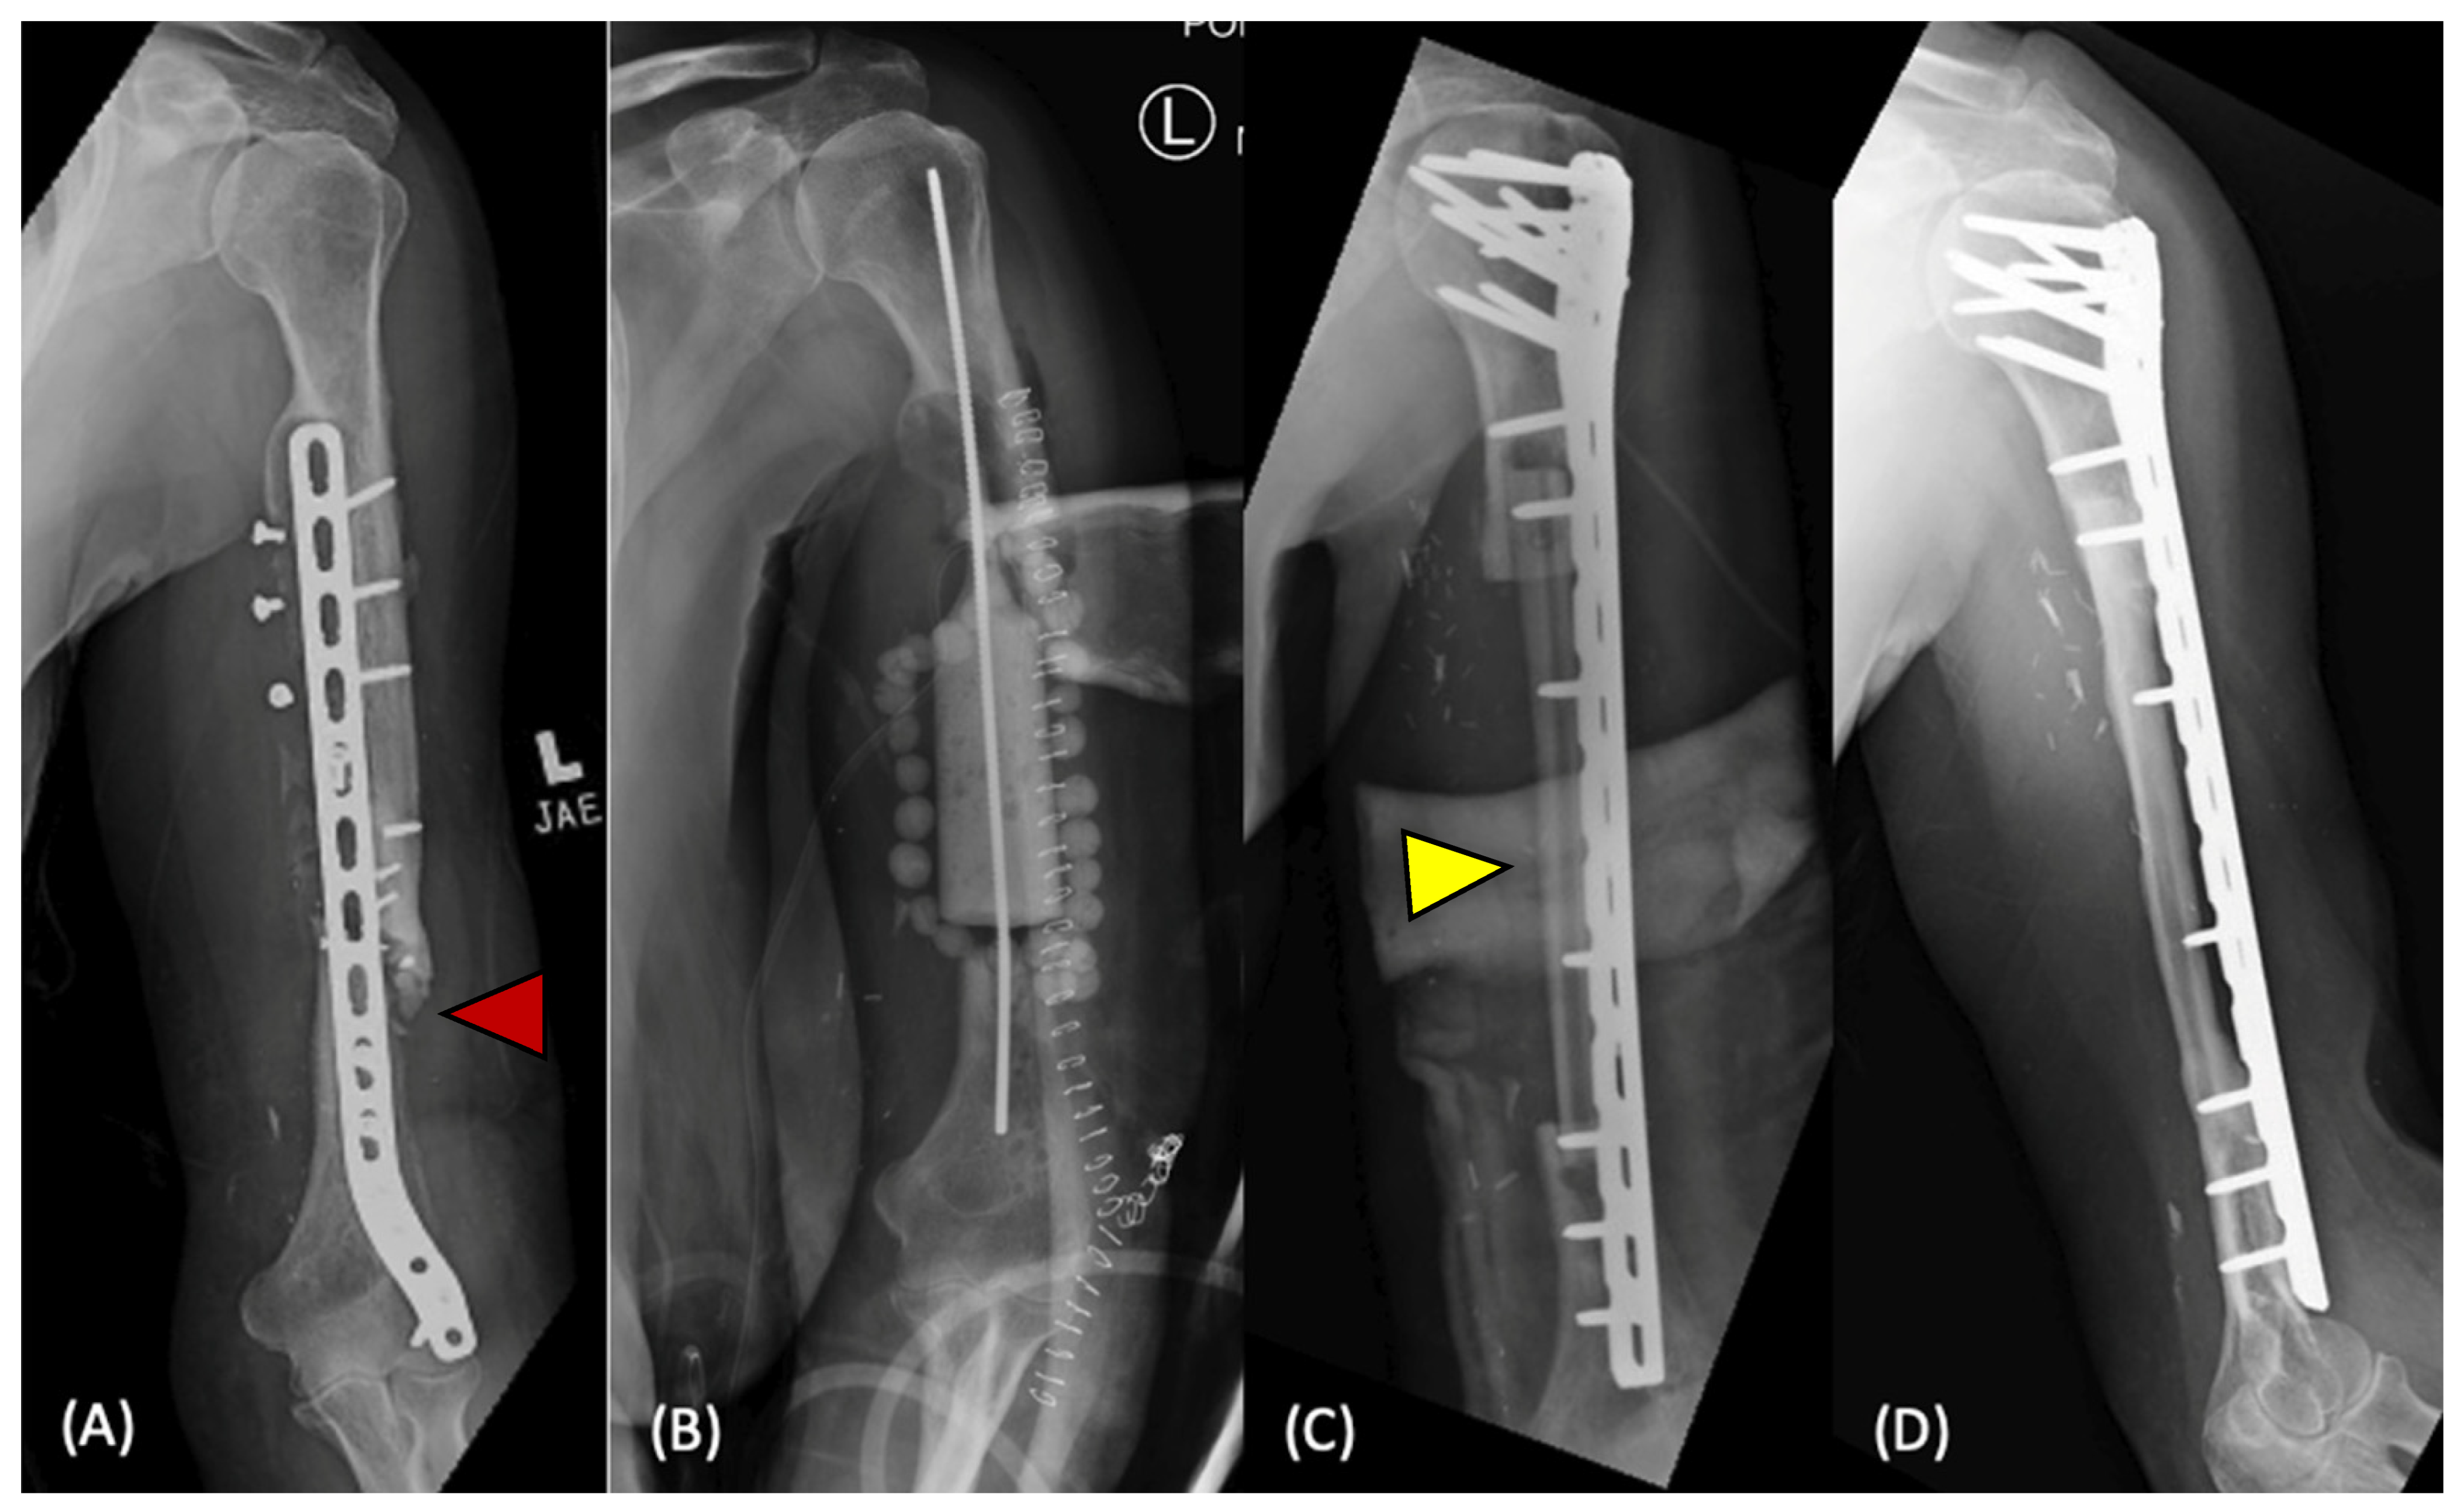

Figure 1.

Management of an infected humeral shaft non-union (red arrow) (A). Initial management with hardware removal, debridement, placement of a temporary antibiotic cement spacer, and antibiotic beads (B). After treatment of the infection, the patient underwent vascularized free fibula transfer (yellow arrow) and revision open reduction internal fixation (C). Graft showed satisfactory incorporation one year after the procedure (D). Reproduced with permission from Mayfield et al. [61].